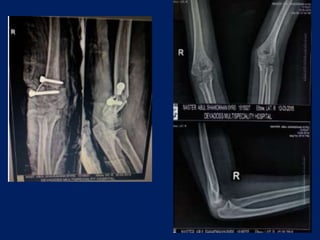

AP VIEW X RAY

 Baumann’s angle (or the humero capitellar angle)

radiographic measurement used to assess the normal

relationships of the distal humerus and is measured

on the AP projection of the elbow.

 Drawing a line parallel to the longitudinal axis of the

humeral shaft as well as a bisecting line parallel to the

lateral condylar physis creates Baumann’s angle.

 A normal angle is 70-75 degrees or within 5 degrees of

the contralateral elbow